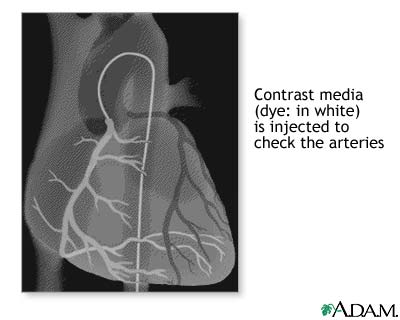

Coronary artery balloon angioplasty - series: Procedure, part 5

Once the catheter has been positioned at the coronary artery origin, contrast media is injected and a series of X-rays (film) are taken to check for any change in the arteries. Following this, the catheter is removed and the procedure is completed.